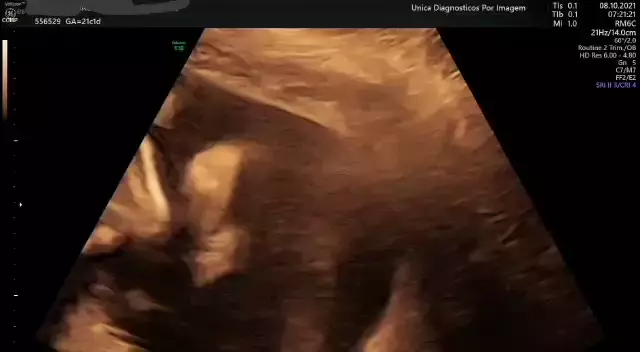

ultrassom 4D obstetrico.